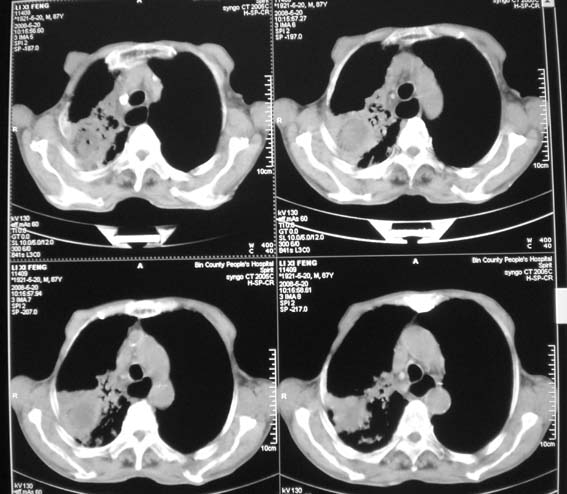

男,87岁,咳嗽、发烧、有黄痰,胸片示肺结核。

右肺上叶尖后段片状不规则致密影,密度欠均匀,相邻胸膜肥厚,纵隔内见多发肿大、钙化淋巴结,考虑为结核,部分坏死

有低密度坏死灶;结合痰检。